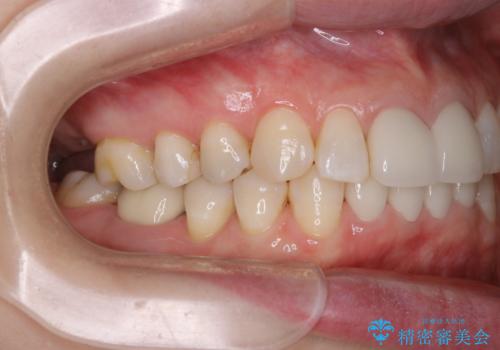

- すき間の部分の歯磨きがしずらく、クリーニング希望で来院されました。今後はセラミックによる治療を考えてとの事でした。PMTC(保険外治療)30分コースを行いました。

PMTC(保険外治療)とは、歯垢・歯石・着色などを除去することです。磨きのこしなどにより歯垢が付着し続けると、歯石に変化していきます。歯石になってしまったら、歯ブラシだけで落とすことができなくなります。そのため歯科医院での専門的な機械・材料を使用してのクリーニングが必要です。